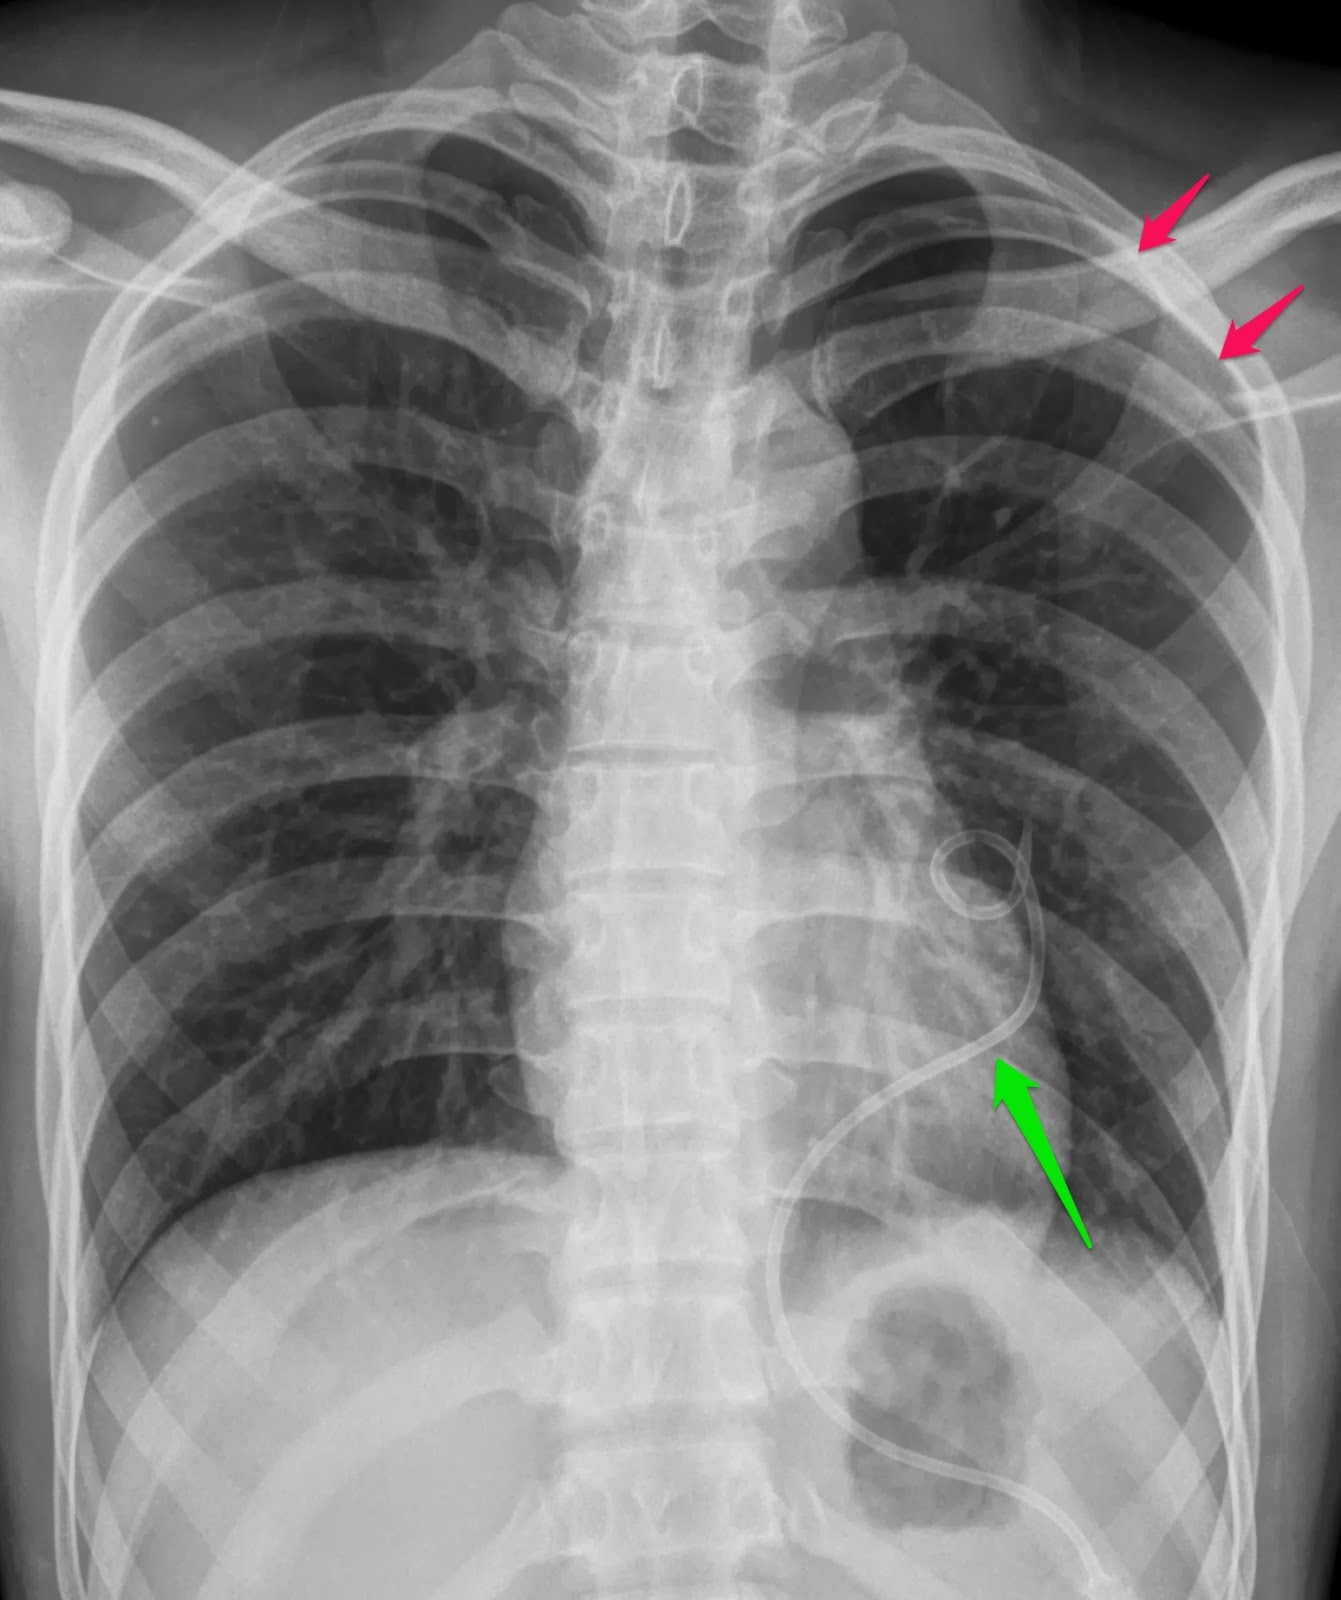

ตัวอย่างภาพผู้ป่วยหลังการใส่สายชนิด Tunneled cuffed double lumen catheter เป็นดังต่อไปนี้

| ภาพตัวอย่างหลังใส่หลอดสวนสำหรับฟอกเลือดชนิด Tunneled Cuffed Double lumen จะเห็นว่ามีส่วนที่ลอดใต่ผิวหนัง (ส่วนที่โค้งตอนบน) และบางส่วนของสายโผล่ออกคนละจุดกับจุดที่หลอดสวนเข้าหลอดเลือดดำ |